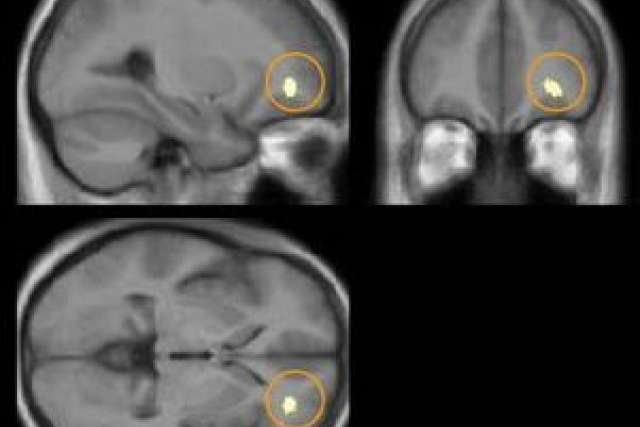

That's the finding from a group of researchers at UCLA who used high-resolution magnetic resonance imaging (MRI) to scan the brains of people who meditate. In a study published in the journal NeuroImage and currently available online (by subscription), the researchers report that certain regions in the brains of long-term meditators were larger than in a similar control group.

Specifically, meditators showed significantly larger volumes of the hippocampus and areas within the orbito-frontal cortex, the thalamus and the inferior temporal gyrus — all regions known for regulating emotions.

The researchers used a high-resolution, three-dimensional form of MRI and two different approaches to measure differences in brain structure. One approach automatically divides the brain into several regions of interest, allowing researchers to compare the size of certain brain structures. The other segments the brain into different tissue types, allowing researchers to compare the amount of gray matter within specific regions of the brain.

The researchers found significantly larger cerebral measurements in meditators compared with controls, including larger volumes of the right hippocampus and increased gray matter in the right orbito-frontal cortex, the right thalamus and the left inferior temporal lobe. There were no regions where controls had significantly larger volumes or more gray matter than meditators.